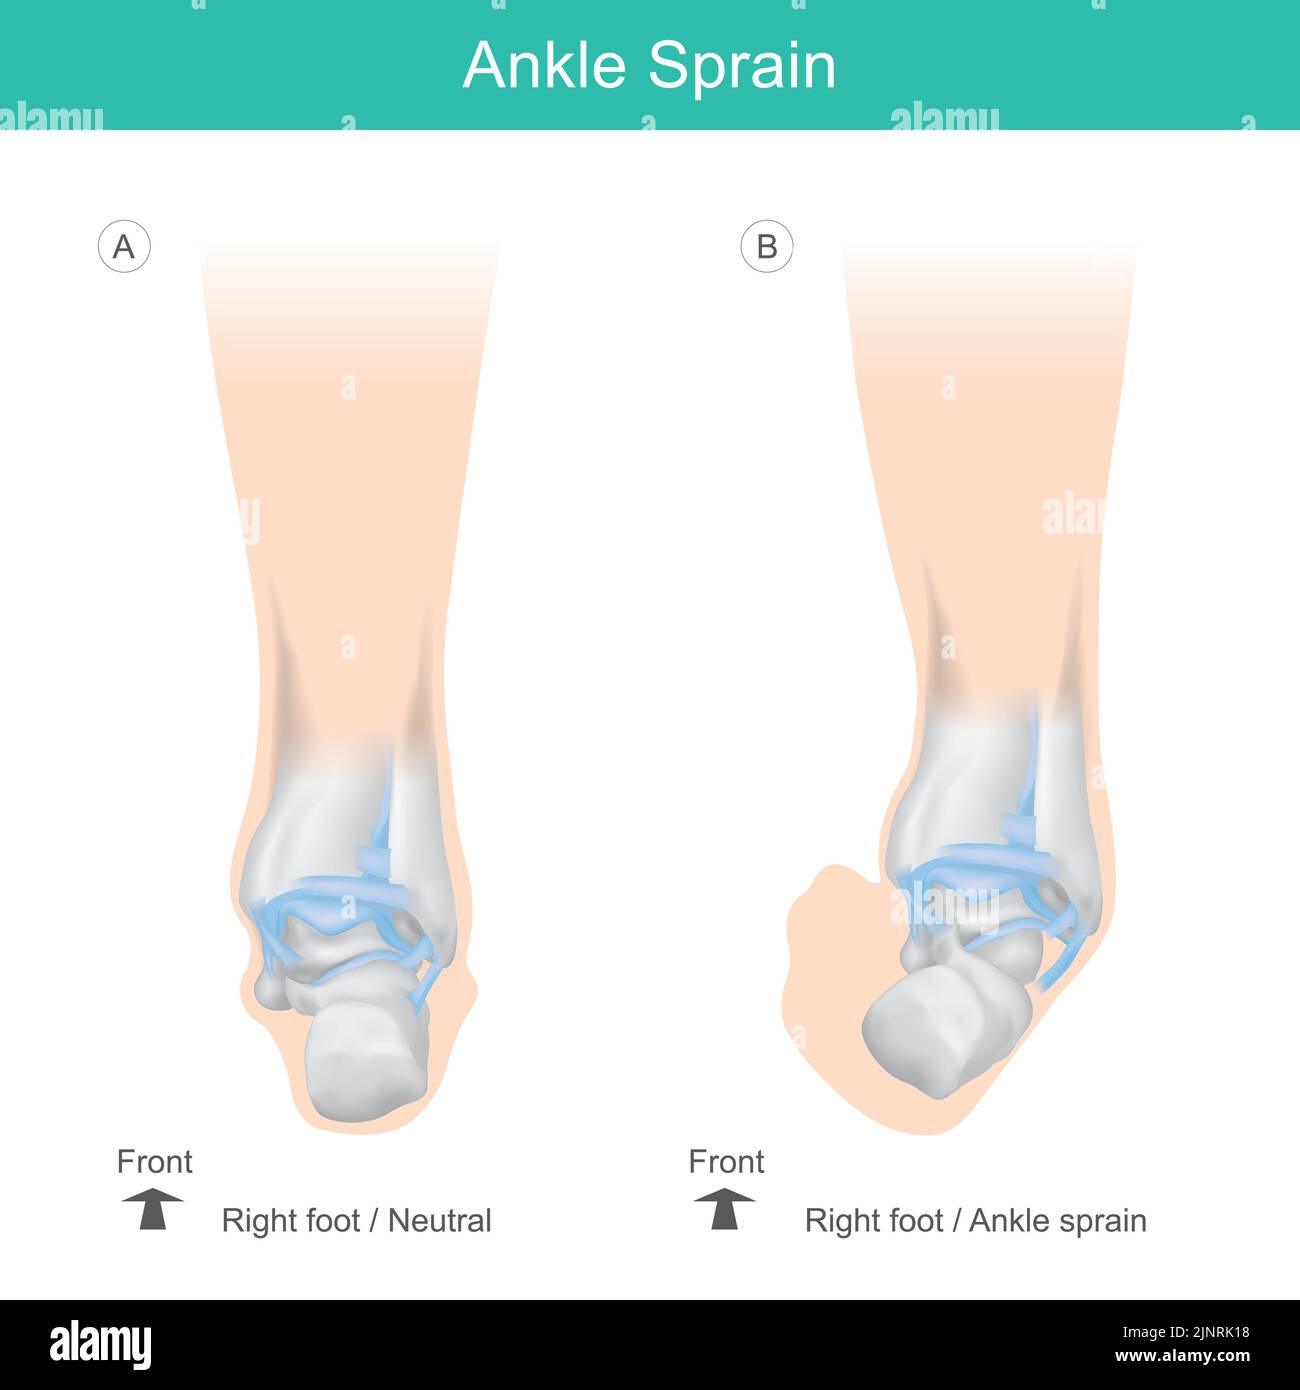

RF2JKN2D2–OS de la cheville humaine, position correcte os de la cheville humaine. Illustration Anatomy Health Care.

RF2JNRK18–Os de cheville de l'homme. Positionnement correct des os de la cheville chez l'homme. Illustration soins de santé.